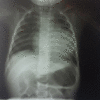

Case presentation: A 9-year-old Caucasian boy presenting with signs and symptoms of heart failure refractory to conventional therapies was admitted to our pediatric cardiology service. As the patient also had psoriasis, and considering the fact that there might be an association between the two conditions, immunosuppressive drugs were administered, which led to a dramatic improvement in heart function.